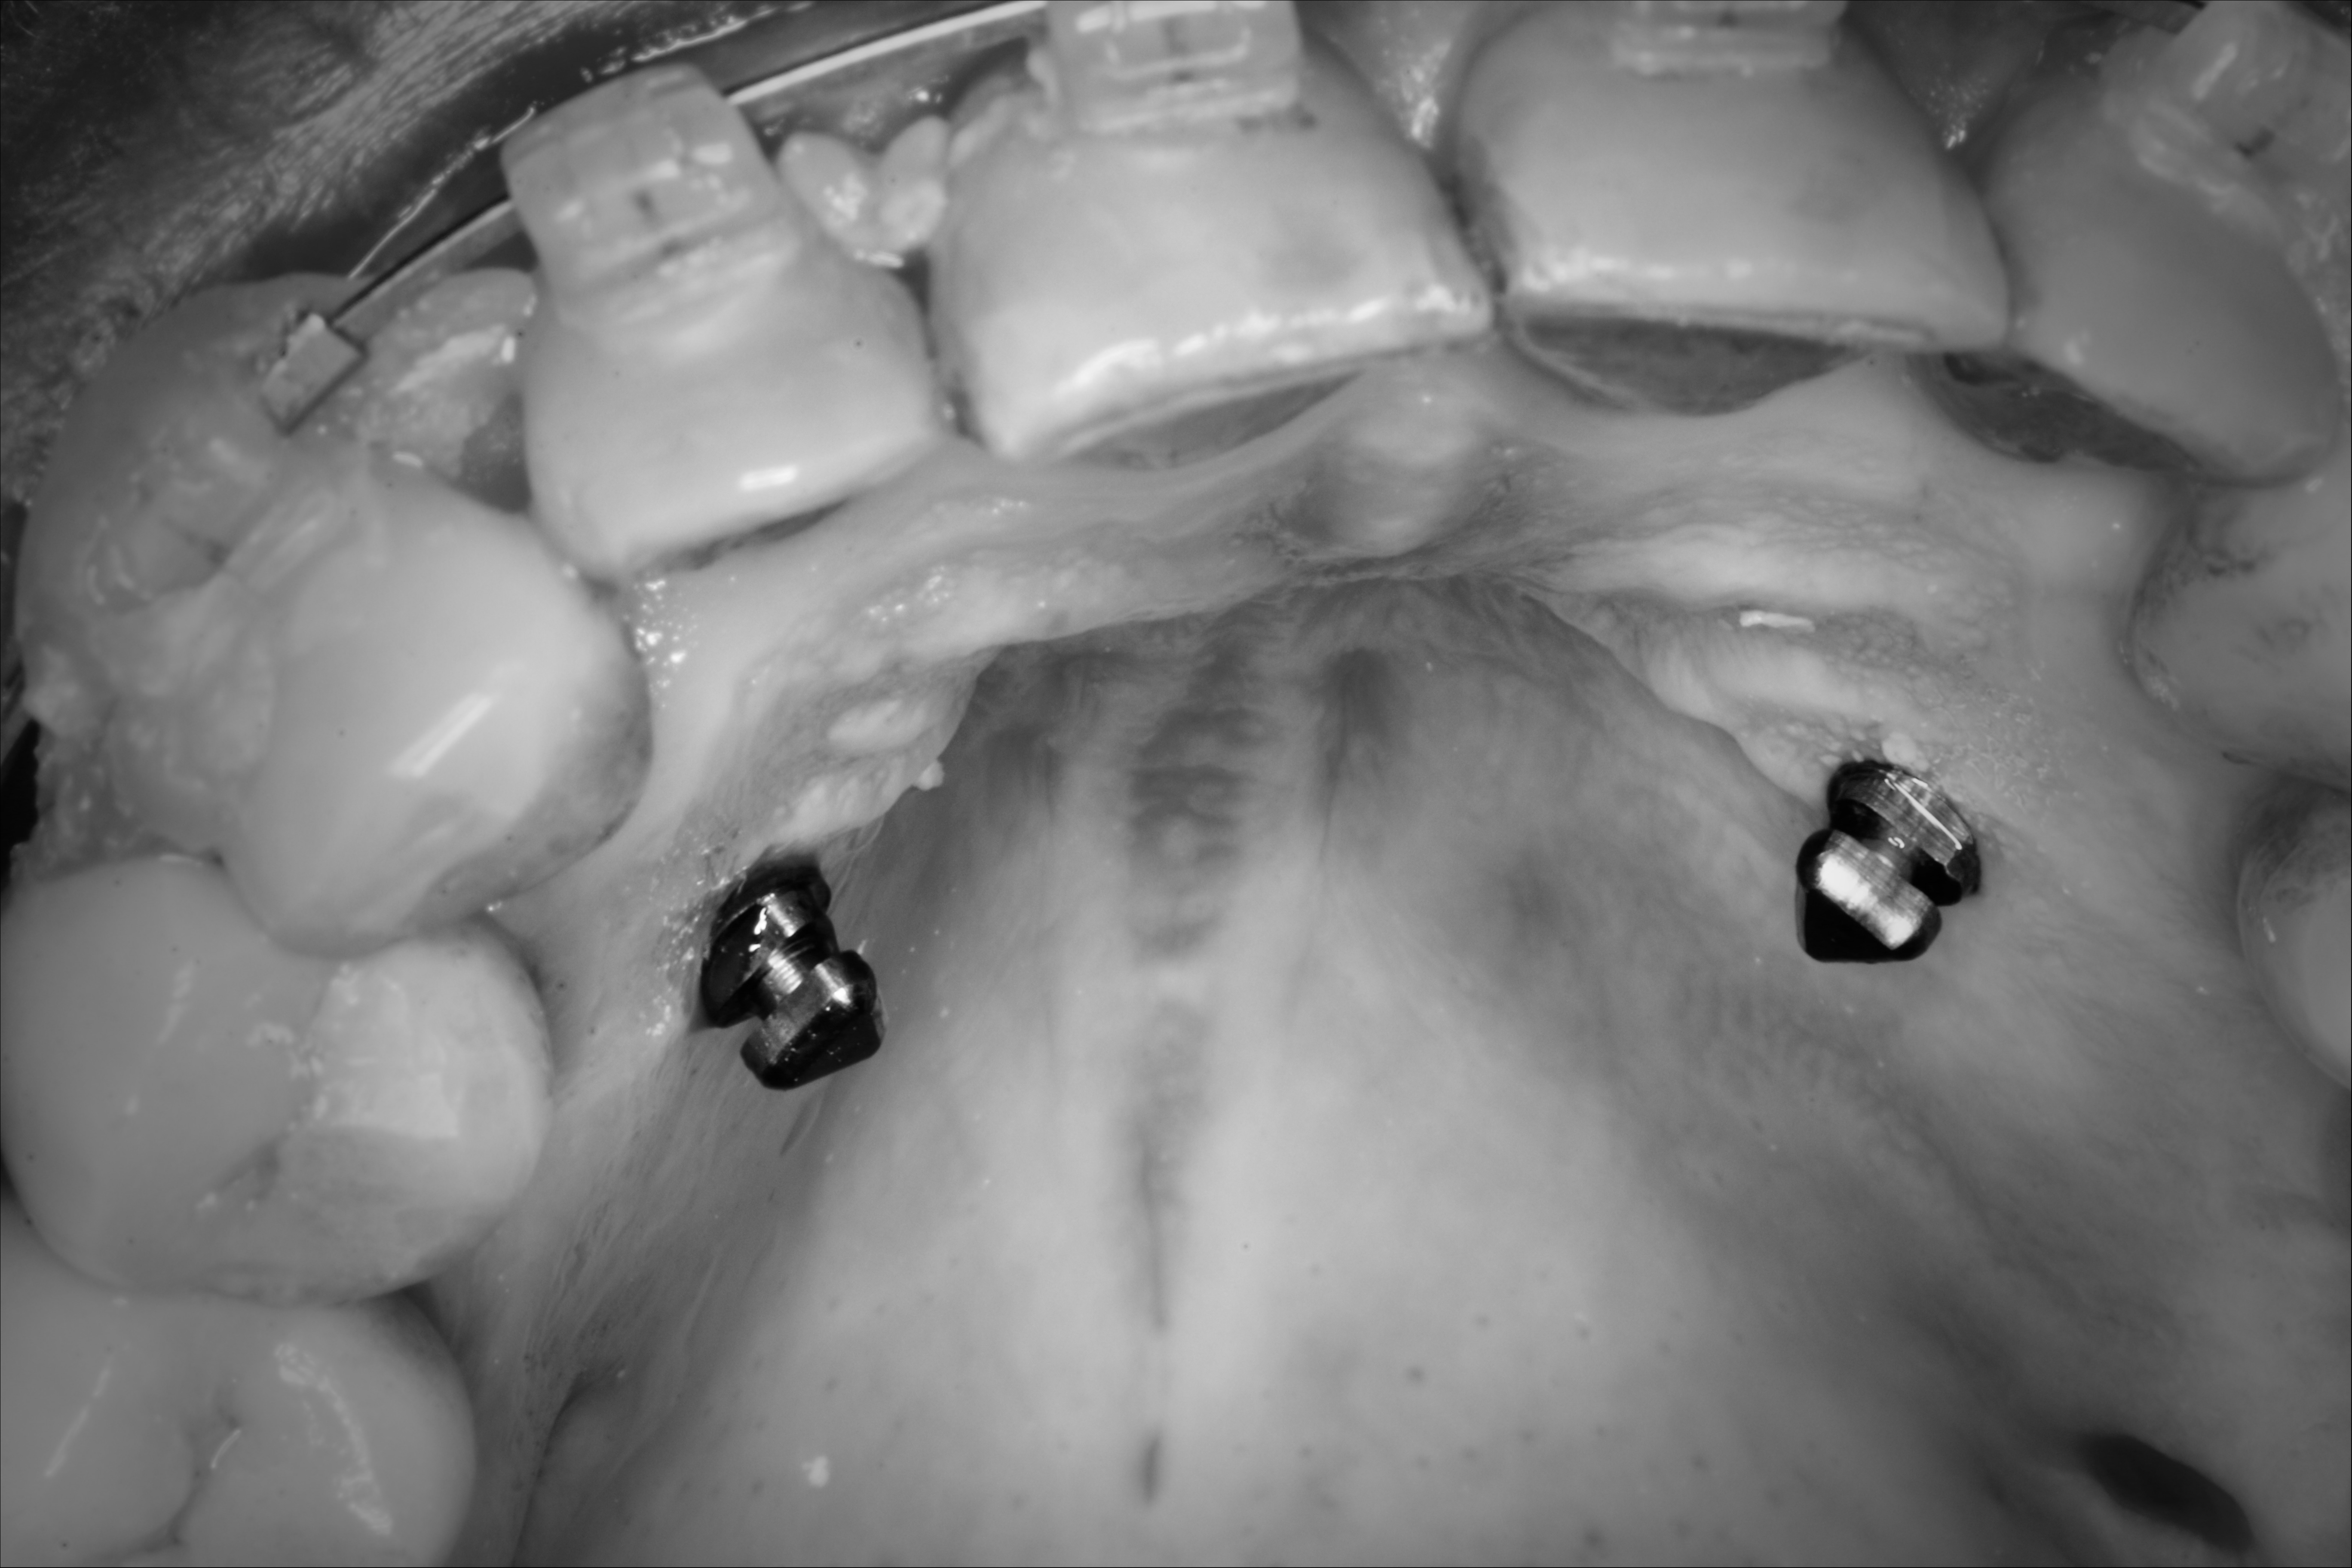

Anyone can do it! Placing Palatal Mini-implants in 3 minutes.

Placing a Palatal Ortodontic Implant in 3 minutes BRIGHTDENTISTRY 4